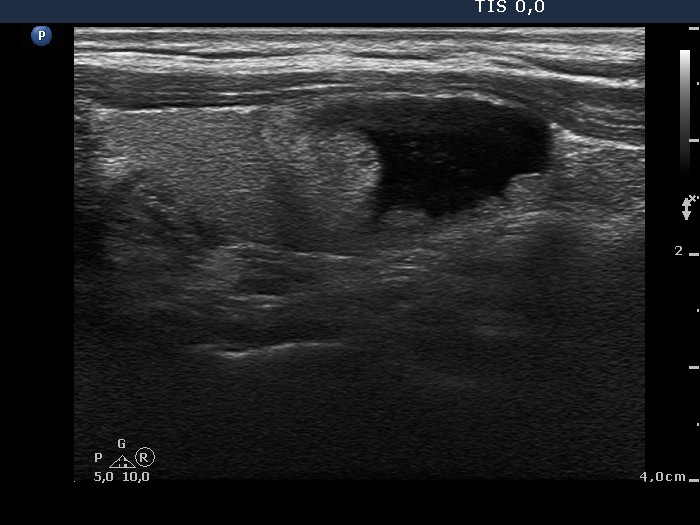

Benign nodular hyperplasia - Case 46. |

Clinical presentation: A 44-year-old woman was referred for evaluation of a nodule which was discovered on a routine examination. The nodule was held as suspicious because of the shape of the solid part of the cyst. The patient had no complaints.

Palpation: a not firm nodule in the right lobe.

Ultrasonography: There was a solitary, cystic-echonormal nodule in the right lobe.

Cytological diagnosis: benign, colloid goiter.